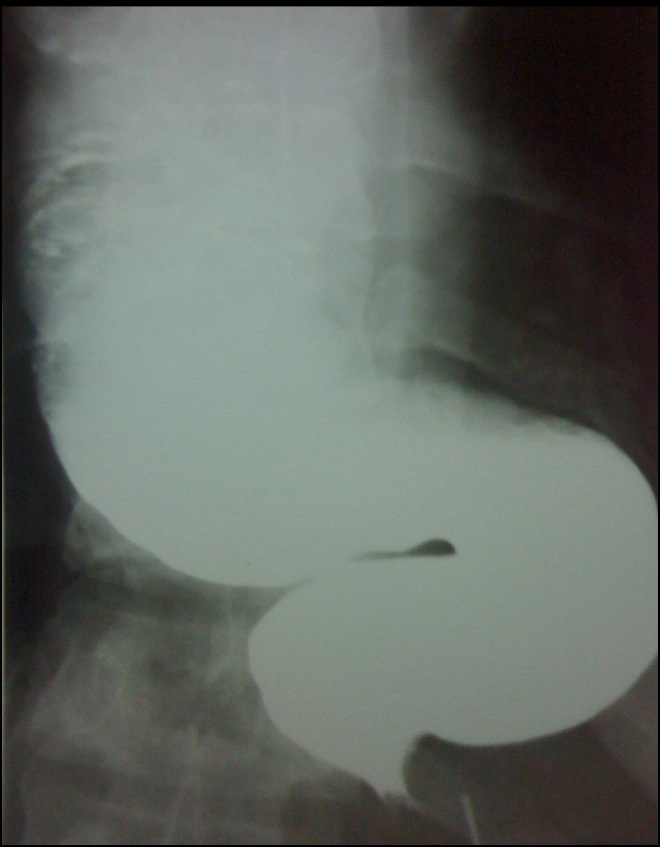

Of the total, 3 corresponded to the male sex and 4 to the female sex. The average age was 54.7 with a range of 35 to 66 years. One case corresponded to a megaesophagus of Chagasic origin, and the other 6 cases were due to recurrence of the Heller-Dor myotomy, which was treated with endoscopic dilations. The treatments performed were: 1 laparoscopic transhiatal esophagectomy and a minimally invasive esophagectomy in the prone position (Figure 2) 4 esophagus ardioplasty procedures, as described in Figure 3, and 1 case of resection of the esophagogastric junction and Roux-en-Y bypass.

Figure 2: Megaeasophagus.